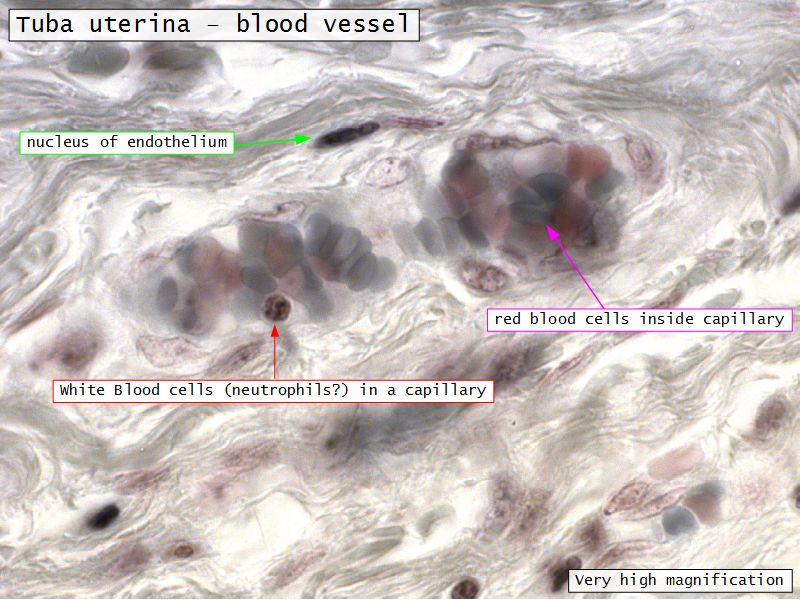

Serosa

- Contains

- Blood vessels

- Lymphatics

- Nerves